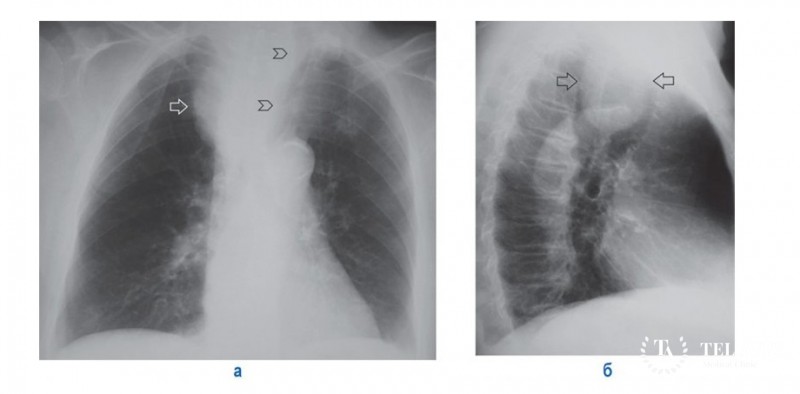

- Рентгенологический осмотр, позволяющий выявить точную локализацию патологического очага, его структуру, размерность;

- Рентгеновское исследование органов грудины;

- Полипозиционная рентгенография;